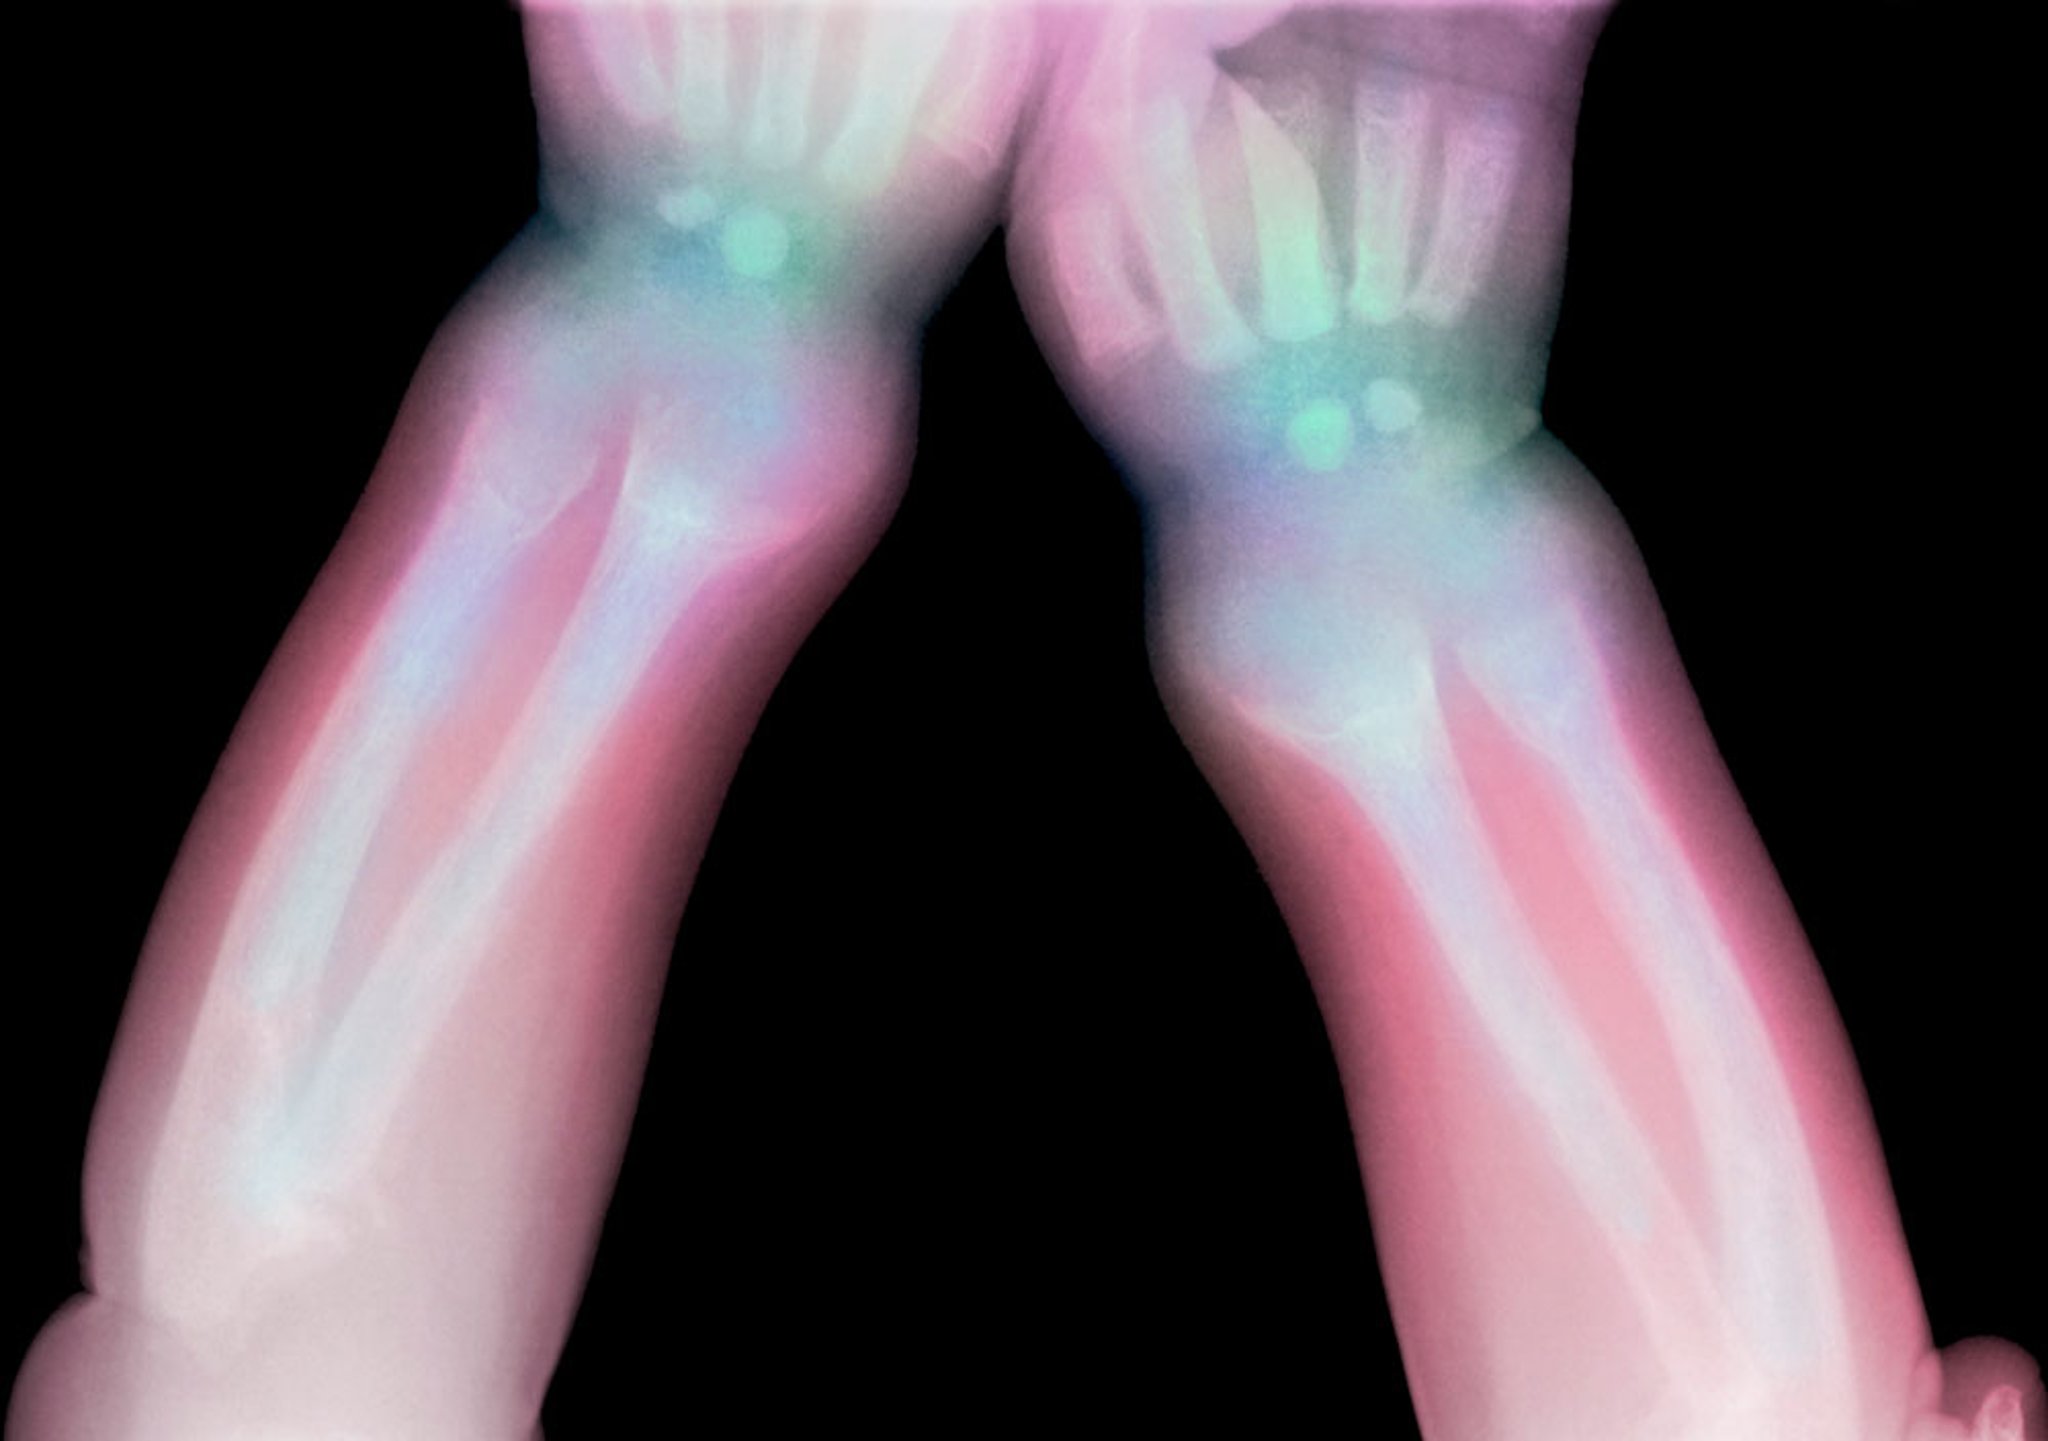

This radiograph shows lucency of the distal radius and ulna in a child with rickets.

Credit DU CANE MEDICAL IMAGING LTD / SCIENCE PHOTO LIBRARY